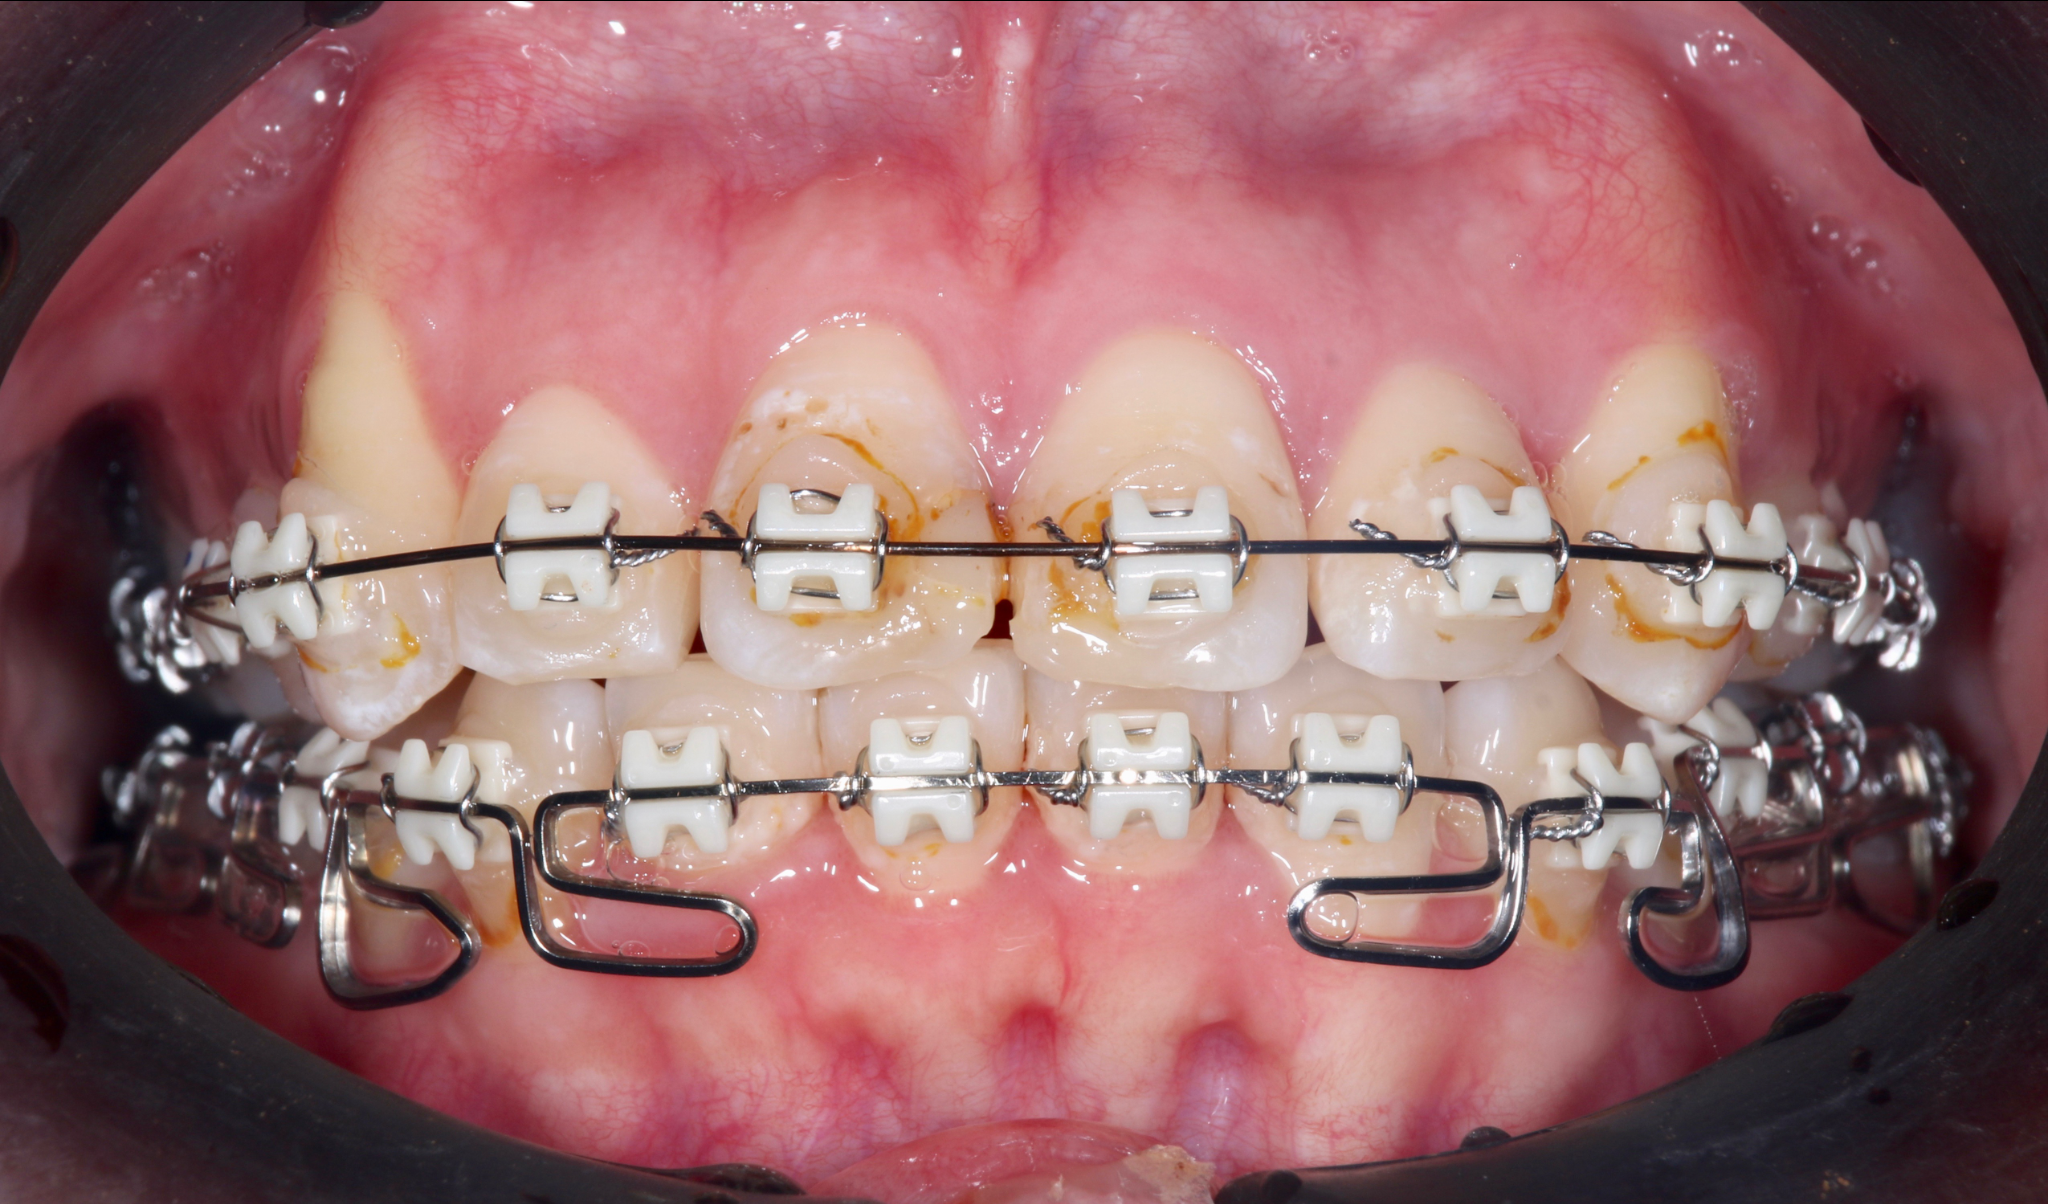

症例1:重度の叢生を矯正治療で改善した症例

術前の状態

術後の状態

治療概要

| 患者さんの状態 | 重度の叢生 |

|---|---|

| 治療内容 | MEAWを用いた矯正治療(非抜歯) |

| 治療期間 | 約2.5年 |

| 治療費用 | 1,320,000円(税込) ※矯正治療費のみです。 |

| 治療のリスク | 歯肉退縮、自由診療、後戻り、口腔内清掃が難しい |